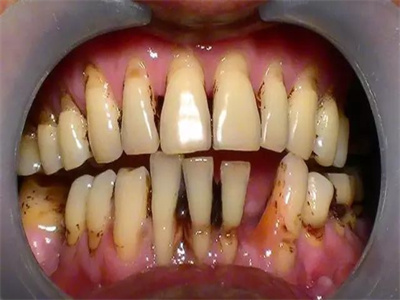

牙龈炎常见的病因是口腔卫生差,不良的口腔卫生使牙菌斑沉积于牙齿与牙龈之间,造成龈沟加深,另外牙结石、不良修复体等也可造成牙龈炎的发生。

牙龈炎是发生于牙龈组织的炎症,患者可出现牙龈出血伴肿胀、发红、正常形态改变和偶尔不适等症状。本病主要由口腔卫生状况差导致,包括口腔不洁、牙菌斑等,诊断依据临床检查,治疗包括专业牙齿清洁和加强家庭口腔卫生。